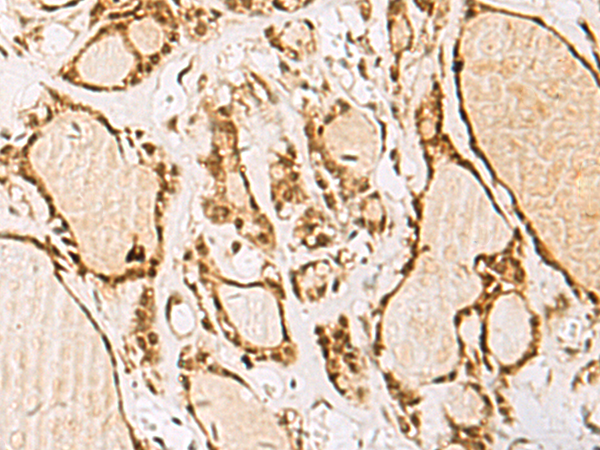

The image is immunohistochemistry of paraffin-embedded Human thyroid cancer tissue using (NIPBL Antibody) at dilution 1/55.

IHC dilution:1:50-1:200